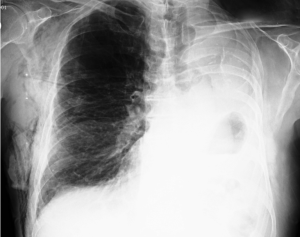

Removal of a single lung leads to a significant loss of pulmonary function. Deterioration in lung function is affected by several factors. Patient’s age, preoperative pulmonary function, time after pneumonectomy and right/left pneumonectomy are important (Figure 1) (6).